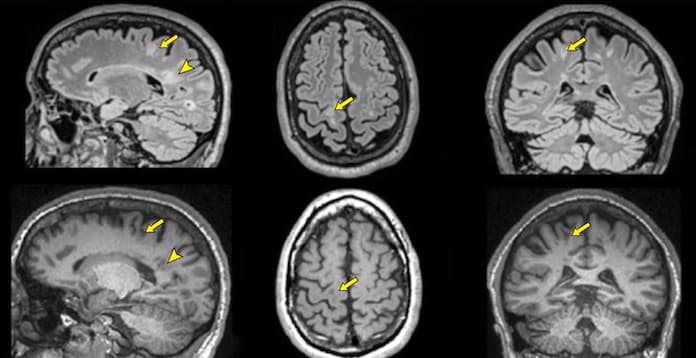

Une étude à grande échelle à partir de l'IRM cérébrale en T1

À l’occasion d’une étude, qui est parue dans la Revue Radiology, le Pr, Ni Shu, du State Key Laboratory of Cognitive Neuroscience and Learning de la Beijing Normal University, (Pékin, Chine) et ses collègues ont utilisé un algorithme d’apprentissage automatique pour former un modèle de prédiction de l'âge du cerveau basé sur des images IRM pondérées en T1 de 974 adultes en bonne santé âgés de 49,3 à 95,4 ans. Le modèle, une fois entraîné, a été appliqué pour estimer la différence d'âge prévue (âge prévu par rapport à l'âge réel) des patients aMCI de la Beijing Aging Brain Rejuvenation Initiative (616 témoins sains et 80 patients aMCI) et de l'Alzheimer's Disease Neuroimaging Initiative (589 témoins sains et 144 patients aMCI).

Les chercheurs ont également examiné les associations entre la différence d'âge prévue et les troubles cognitifs, les facteurs de risque génétiques, les biomarqueurs pathologiques de la MA et la progression clinique chez les patients aMCI. Les résultats ont montré que les patients aMCI avaient des trajectoires de vieillissement cérébral distinctes de la trajectoire de vieillissement normale typique, et le modèle de prédiction de l'âge cérébral proposé pourrait quantifier les écarts individuels par rapport à la trajectoire de vieillissement normale typique chez ces patients. La différence d'âge prédite s’est, d’autre part, avérée significativement associée à une déficience cognitive individuelle des patients aMCI dans plusieurs domaines, notamment la mémoire, l'attention et la fonction exécutive.

"Le modèle prédictif que nous avons généré était très précis pour estimer l'âge chronologique des participants en bonne santé en se basant uniquement sur les images IRM, ont rapporté les chercheurs. En revanche, pour l'aMCI, le modèle a estimé que l'âge du cerveau était supérieur de 2,7 ans en moyenne à l'âge chronologique du patient."

Le modèle a en outre montré que les patients faisant l’objet d’une aMCI qui évolue présentent plus d'écarts par rapport au vieillissement normal typique que les patients aMCI stables, et que l'utilisation du score de différence d'âge allié à d'autres biomarqueurs spécifiques à la MA pourrait mieux prédire la progression de l'aMCI. Les porteurs d'apolipoprotéine E (APOE) ε4 ont montré des différences d'âge prédites plus importantes que les non-porteurs, et les patients positifs à l'amyloïde ont montré des différences d'âge prédites plus importantes que les patients négatifs à l'amyloïde.